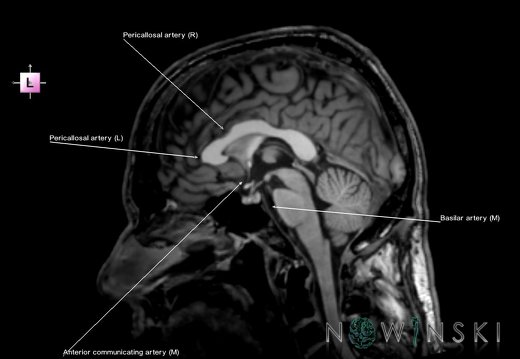

G6.T15.2.V2.P20.Intracranial arteries–Triplanar